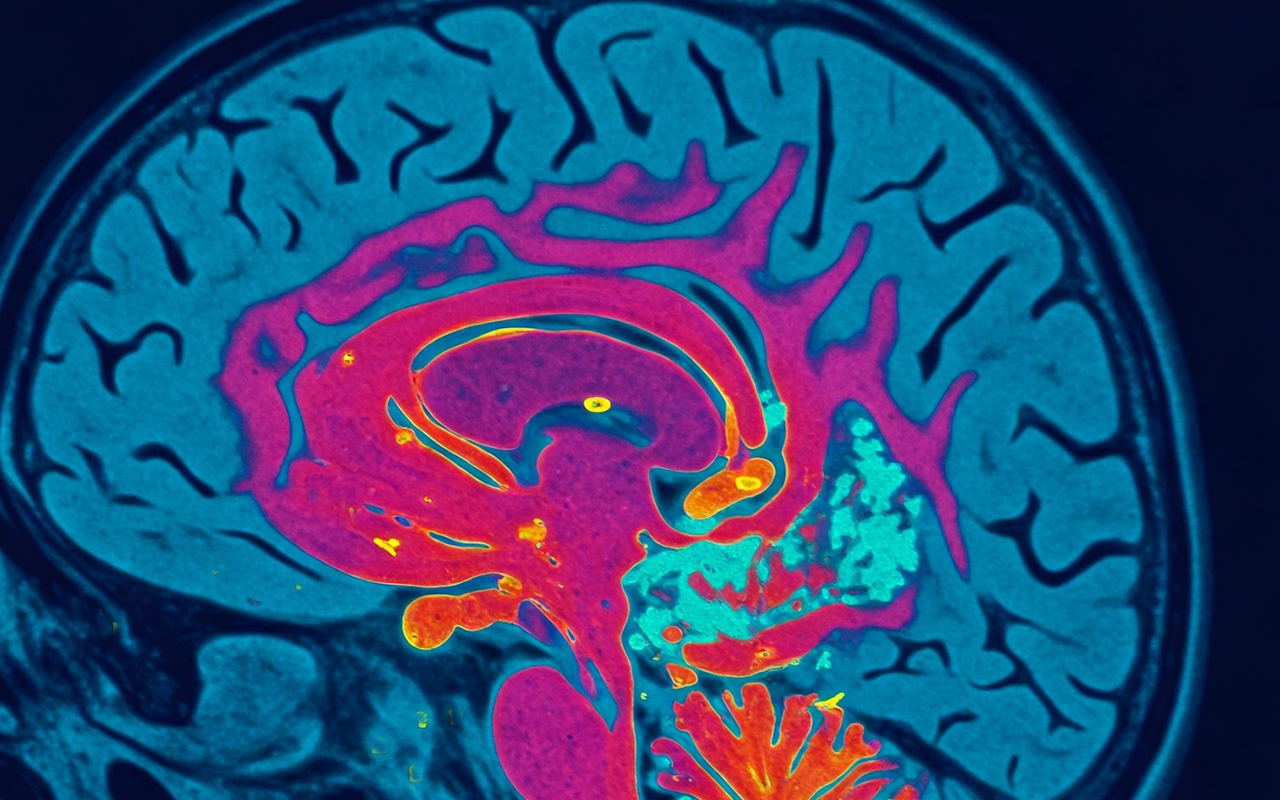

뇌이미지.png 살찌는 뇌 만들어지면 체중 증가로 이어진다?

흔히 ‘살찌는 뇌’라고 불리는 이 현상은 고열량·고당분 식단이 뇌 기능을 변화시키는 것을 의미한다. 특히 뇌의 시상하부에 염증이 생기면 식욕 조절이 어려워지고, 에너지 대사가 원활하지 않아 과식과 비만을 유발할 수 있다.

이뿐만이 아니다. 뇌의 보상 시스템이 둔화되면서 단 음식이나 기름진 음식에서 쾌감을 얻기 어려워지고, 점점 더 강한 자극을 필요로 하게 된다. 쉽게 말해, 패스트푸드와 초콜릿이 계속 당기는 이유도 뇌가 이미 고열량 식단에 적응해 버렸기 때문이라는 것이다.